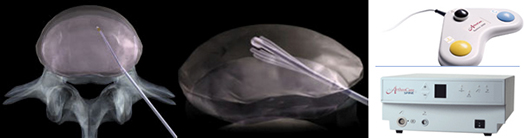

신경성형술영상, 우측의 기구를 이용해 병병부위에 접근하여 풍선을 이용한 신경 감압술

<Neuroplasty image, Approaching the target area using an instrument (right) for nerve decompression>